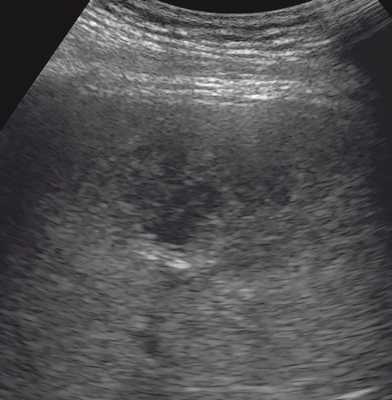

Печень увеличена в размерах: переднезадний размер правой доли 14,3 см (N до 12,5 см), вертикальный размер правой доли 19,0 см (N до 15,0 см), переднезадний размер левой доли 9,3 см (N до 7,0 см). Диафрагмальный край ровный. Структура паренхимы печени неоднородная с наличием в правой доле в проекции V сегмента образования сниженной эхогенности, с несколько нечеткими контурами, размерами до 6,5 х 4,6 х 4,8 см, выраженно неоднородной структуры с наличием в центральных отделах участка умеренно повышенной эхогенности неоднородной структуры размерами 5,8 х 4,8 х 4,2 см, аваскулярного (рис. 1). По периферии образования - деформация сосудистого рисунка (рис. 2). Эхогенность печени обычная. Внутри- и внепеченочные желчные протоки не расширены, стенки их уплотнены. Диаметр воротной вены 1,2 см.

Рис. 1. В-режим. В правой доле печени в проекции V сегмента визуализируется образование сниженной эхогенности с нечеткими контурами выраженно неоднородной структуры с наличием в центральных отделах участка умеренно повышенной эхогенности неоднородной структуры.